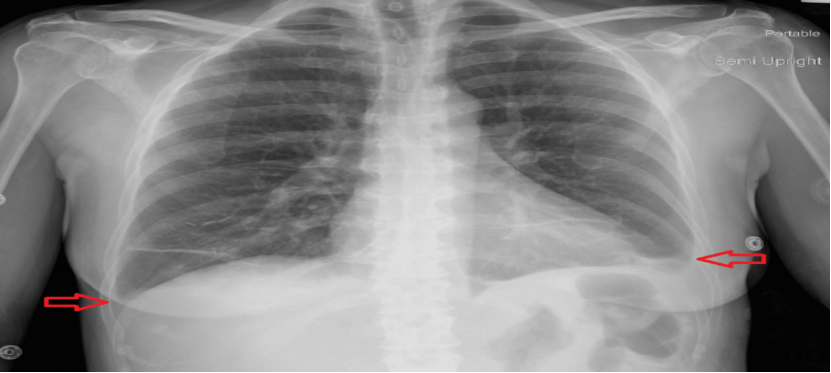

(1) 下肢B超:检查结果排除深静脉血栓形成(2)心电图:显示为窦性心律,存在 R 波递增不良(QTc 485ms)(图1),可排除急性冠脉综合征;(3)胸部 X 线(入院时):可见双侧斑片状阴影及双侧胸腔积液(图2);(4)病原学检查:入院时血培养、尿培养结果均为阴性,且住院期间无感染相关症状与体征,因此双侧斑片状阴影由感染因素导致的可能性较低,更倾向于与急性心力衰竭相关;(5)肺血管 CTA:因患者存在心悸、呼吸急促症状且 D - 二聚体水平轻度升高,遂完善此项检查以排除肺栓塞。结果显示双侧中量胸腔积液、轻度间质性肺水肿及轻度心脏肥大,提示存在充血性心力衰竭(CHF)(图 3、图 4),同时可见散在肺部阴影;(6)经胸超声心动图(TTE):显示左右心室大小正常、收缩功能正常,无局部壁运动异常;左心房大小为 2.93cm(正常范围 1.9-4.0cm),处于正常水平;肺动脉收缩压(PASP)为 34mmHg,存在轻度同心性左心室肥大,心室射血分数为 55%-60%。 (7)核素心肌灌注显像负荷试验:因心电图异常进行此项检查,未发现可逆性缺损,表明无心肌缺血;(8)腹部 / 盆腔 CT:患者肝炎免疫检测结果为阴性,肝转氨酶升高大概率由充血性心力衰竭(CHF)继发的充血性肝淤血引起。为进一步明确情况,行腹部 / 盆腔 CT 检查,显示存在胆结石、胆囊壁增厚 / 水肿、门静脉周围水肿所致的轻度肝肿大,同时伴有新出现的轻度全身性水肿及少量盆腔积液;(9)胸部 X 线(出院时):显示肺充血消退,双侧胸腔积液较入院时减少(图 5)。

图2